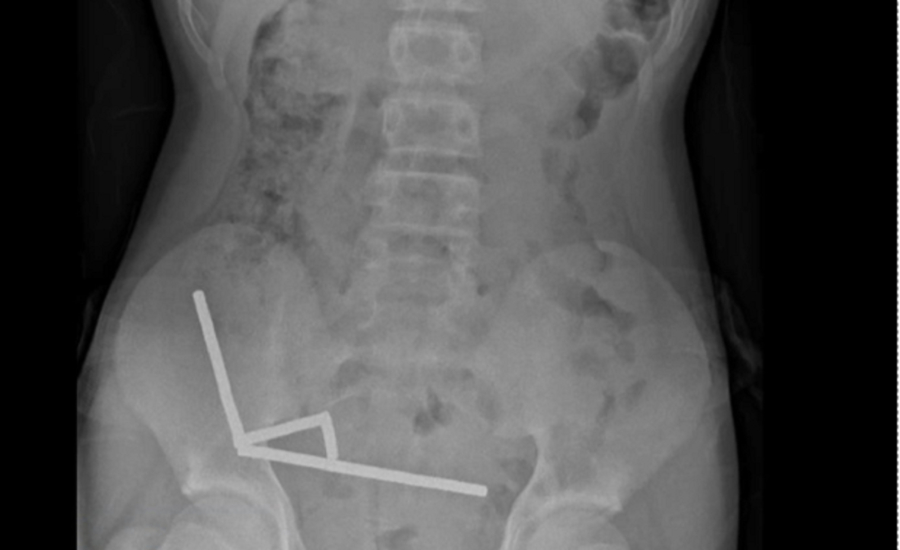

Ν. Ζηλανδία: Χειρουργοί αφαίρεσαν 80-100 μαγνήτες από το έντερο 13χρονου

Ο 13χρονος αγόρασε τους μαγνήτες από το Temu και τους κατάπιε.